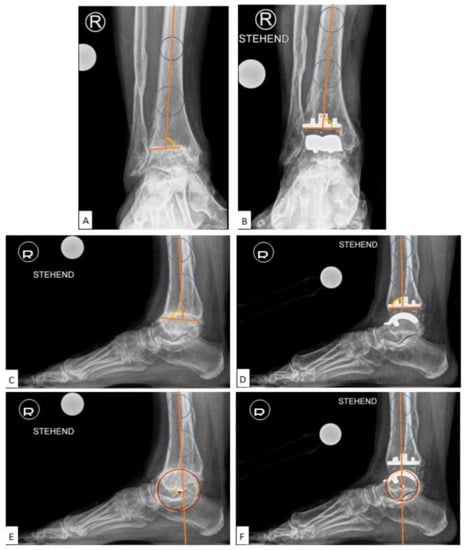

The medial distal tibial articular angle (mDTAA, degrees) [18] on the ankle OA as well as on the TAA as medial tibial component coronal angle were used to identify coronal alignment, measured on the anteroposterior radiograph as the medial angle subtended by the anatomic axis of the tibia and the tibial plafond line or inferior border of the tibial component, with positive values equal to valgus result and negative values equal to varus result (Figure 2A,B). The sagittal alignment assessed was by the anterior distal tibial articular angle (aDTAA, degrees) [19] on the ankle OA and on the TAA as anterior tibial baseplate angle [14,20] on the lateral radiograph, measured as the anterior angle formed from the anatomic axis of the tibia and the line connecting the distal points on the anterior and posterior tibial articular surface or inferior border of the tibial component (Figure 2C,D).

Figure 2.

Preoperative and Postoperative Radiological Measurements. (A): Medial distal tibial articular angle (mDTAA) on the ankle osteoarthritis (OA), (B): Medial distal tibial articular angle (mDTAA) on the total ankle arthroplasty (TAA) as medial tibial component coronal angle, (C): Anterior distal tibial articular angle (aDTAA) on the ankle OA, (D): Anterior distal tibial articular angle (aDTAA) on the TAA as anterior tibial baseplate angle. Lateral talar station (LTS). (E): Preoperative on the ankle OA, (F): Postoperative on the TAA.

Among the methods listed above, we utilised the LTS (Lateral Talar Station, mm) technique described in the literature as the most reproducible and least sensitive to sagittal ankle position, with defined normal ranges, to quantify sagittal talar position. The LTS method as described by Veljkovic et al. [16]—a modification of the previously described TibCOR measurement by Magerkurth et al. [12]—measures the distance between the tibial long axis, defined as a line joining the centre of two circles in the tibia (10 cm and 5 cm from tibial plafond), and a perpendicular line extending to the centre of rotation of the talus (as an average of the two condylar centres of rotation), reported in millimetres. Values were defined as high if the centre of the circle was anterior to the tibial axis (>3.1496 mm) and low if lying posterior to the tibial axis (<−0.8076 mm) [16] (Figure 2E,F). In order to get more insight into the LTS measurement, the following subgroups analyses were performed: LTS (overall total values), LTS-A: preoperatively anteriorly subluxated ankle OA cases, LTS-P: preoperatively posteriorly subluxated ankle OA cases, LTS-N: preoperatively non-subluxated ankle OA cases.

The mean LTS (Lateral Talar Station, mm) values for all patients were 3.95 mm ± SE 0.78 (range: −11.52 to 13.89) preoperatively and 1.14 mm ± SE 0.63 (range: −10.76 to 11.75) at 12 months, with a statistically significant difference between preoperative and 12-month follow-up (p = 0.01). The mean LTS for 27 TAA with anterior subluxation (LTS-A) preoperatively was 7.99 mm ± SE 0.54 (range: 3.30–13.89) and 1.59 mm ± SE 0.71 (range: −5.72 to 11.75) at 12 months postoperatively, with a highly statistically significant difference between preoperative and 12-month values (p < 0.00001). The mean LTS for 16 TAA with no subluxation (LTS-N) preoperatively was 1.22 ± SD 1.02 (range: −0.63 to 2.70) and 2.01 ± SD 4.82 (range: −10.67 to 10.48) at 12 months postoperatively, with no statistically significant difference between preoperative and 12-month values (p = 0.53). The mean LTS for 7 TAA with posterior subluxation (LTS-P) preoperatively was −5.44 ± SD 3.63 (range: −11.52 to −2.17) and −2.55 ± SD 5.13 (range: −10.76 to 3.20) at 12 months postoperatively with, no statistically significant difference between preoperative and 12-month values (p = 0.25) (Table 3) (Figure 3A,B).

Figure 3.

Case with Centralization of Talus after Implantation of VANTAGE Mobile Bearing Total Ankle Arthroplasty. The talar centre of rotation/Lateral Talar Station (LTS) converged toward the longitudinal tibial axis from 10 mm preoperatively (A) to 2 mm postoperatively in 12 months follow-up radiograph (B).